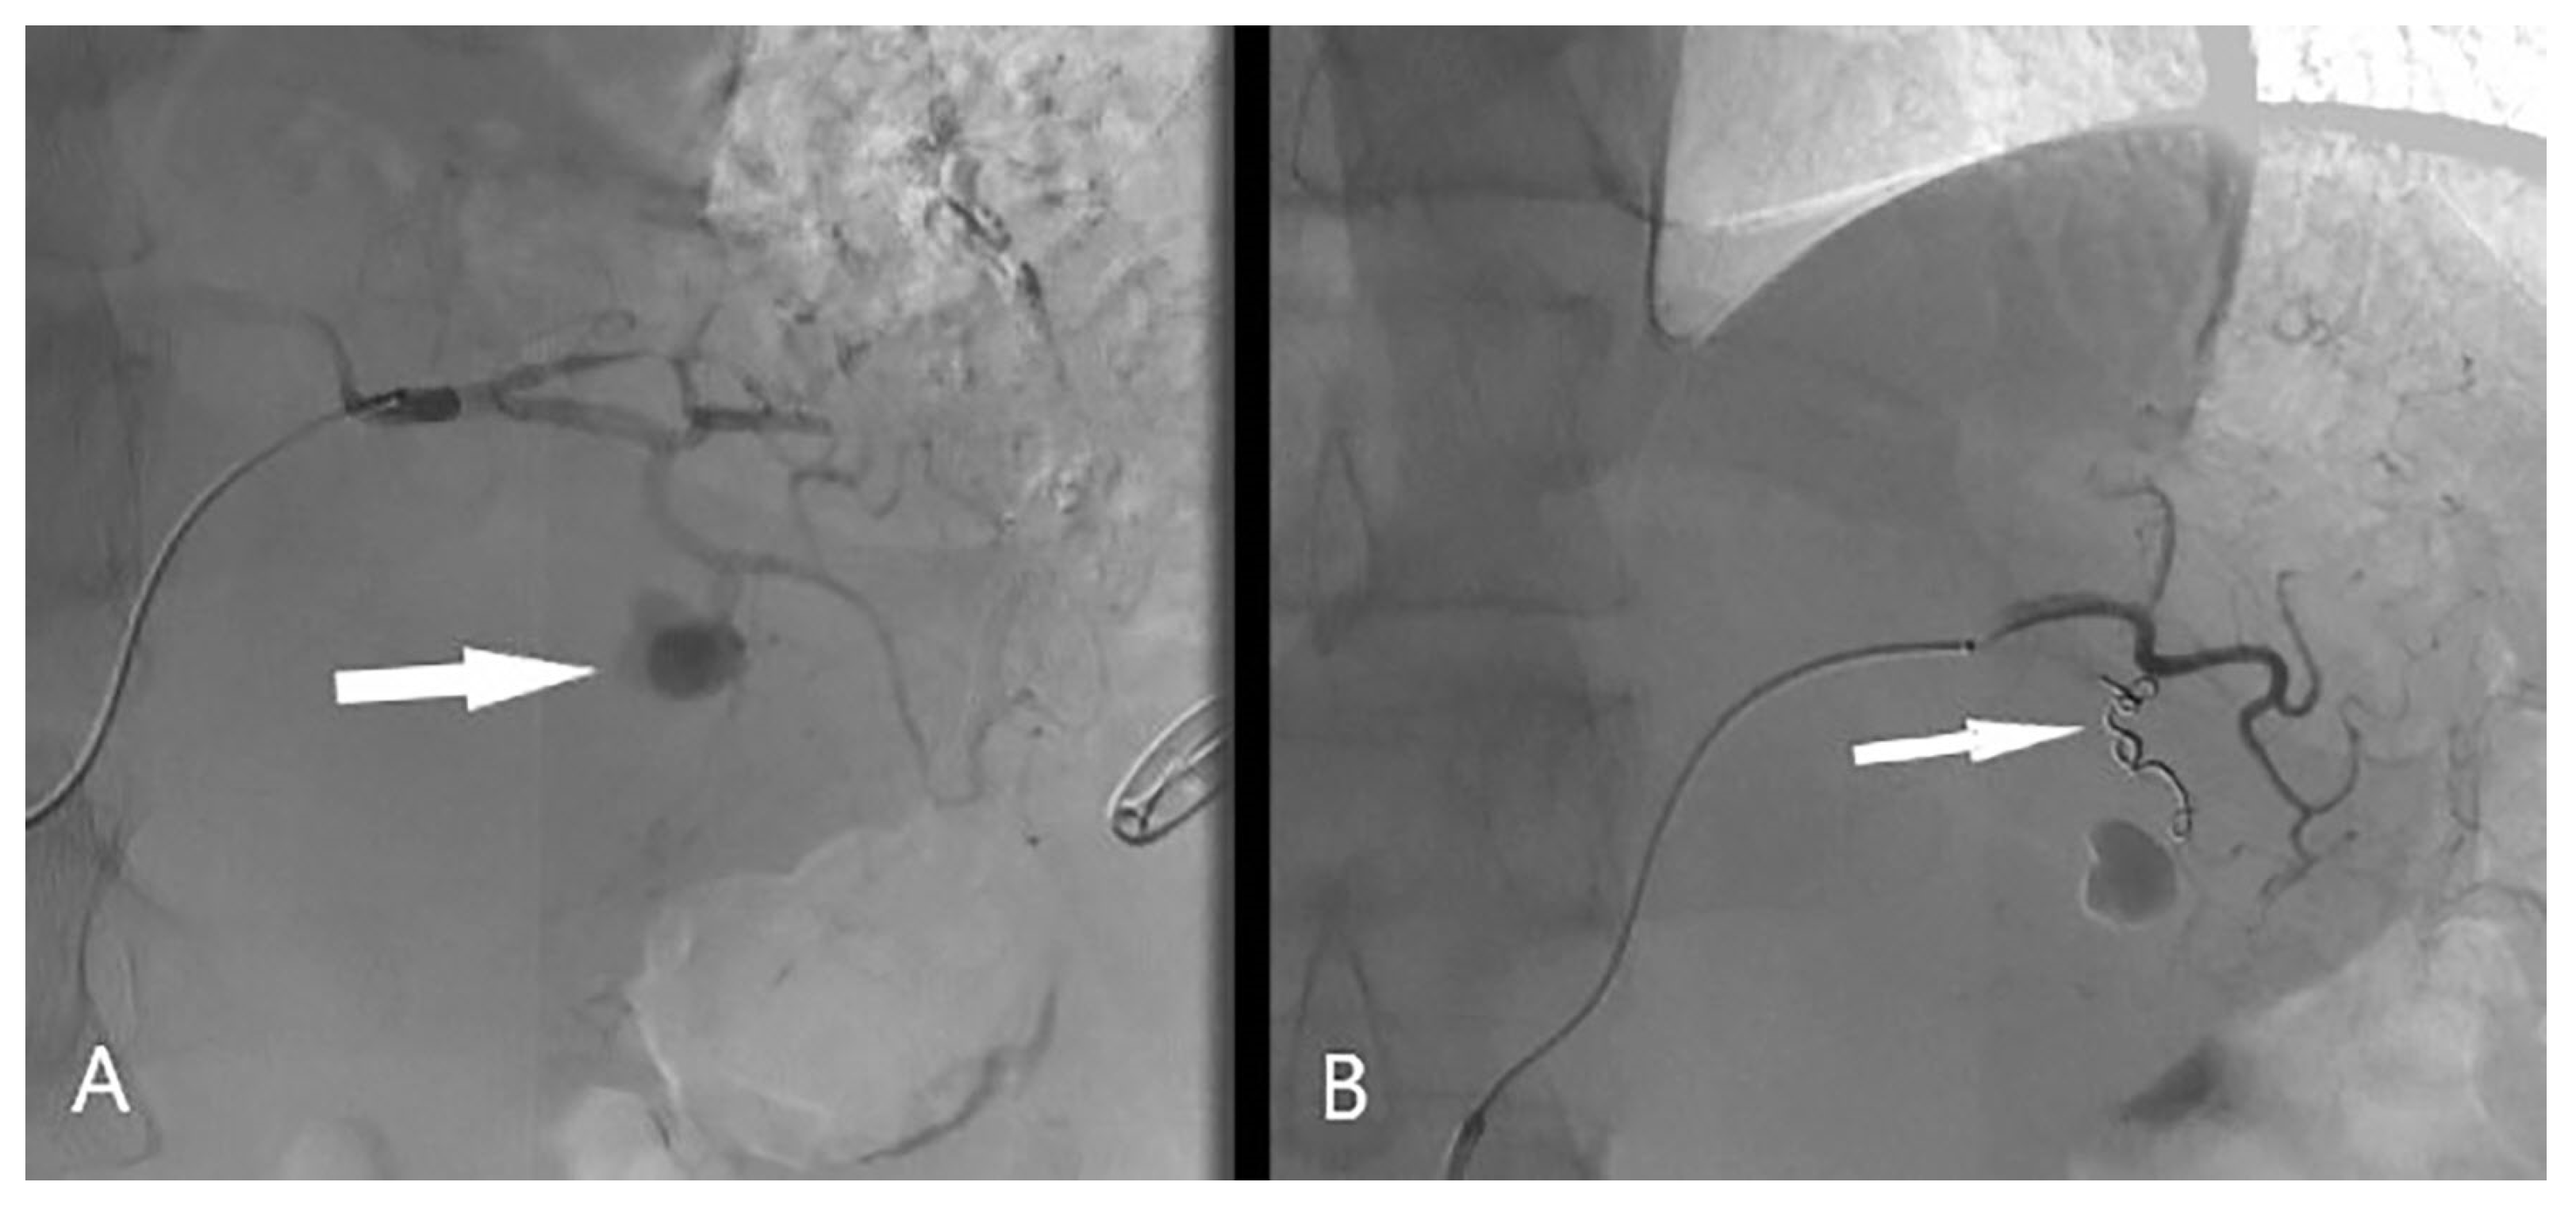

2. Case Report